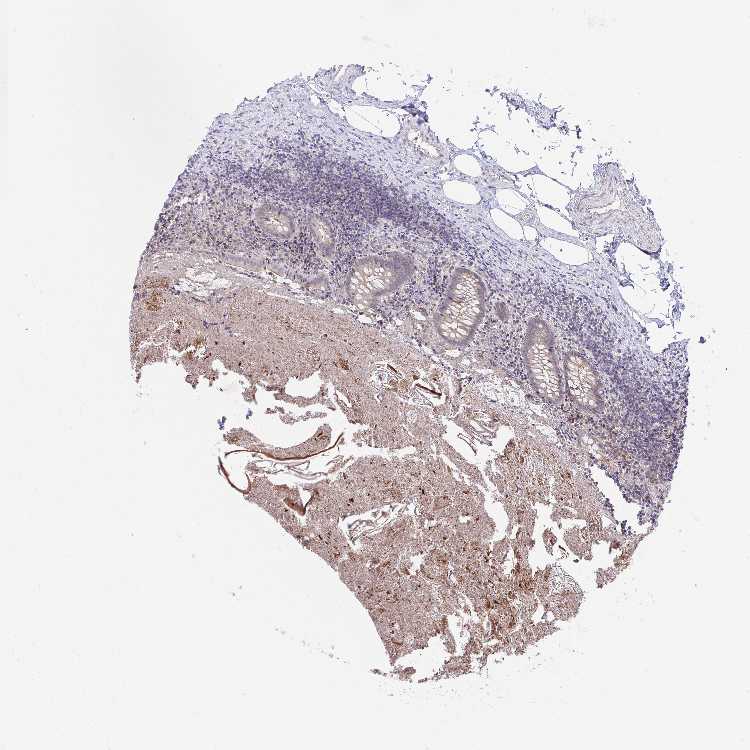

C5orf24